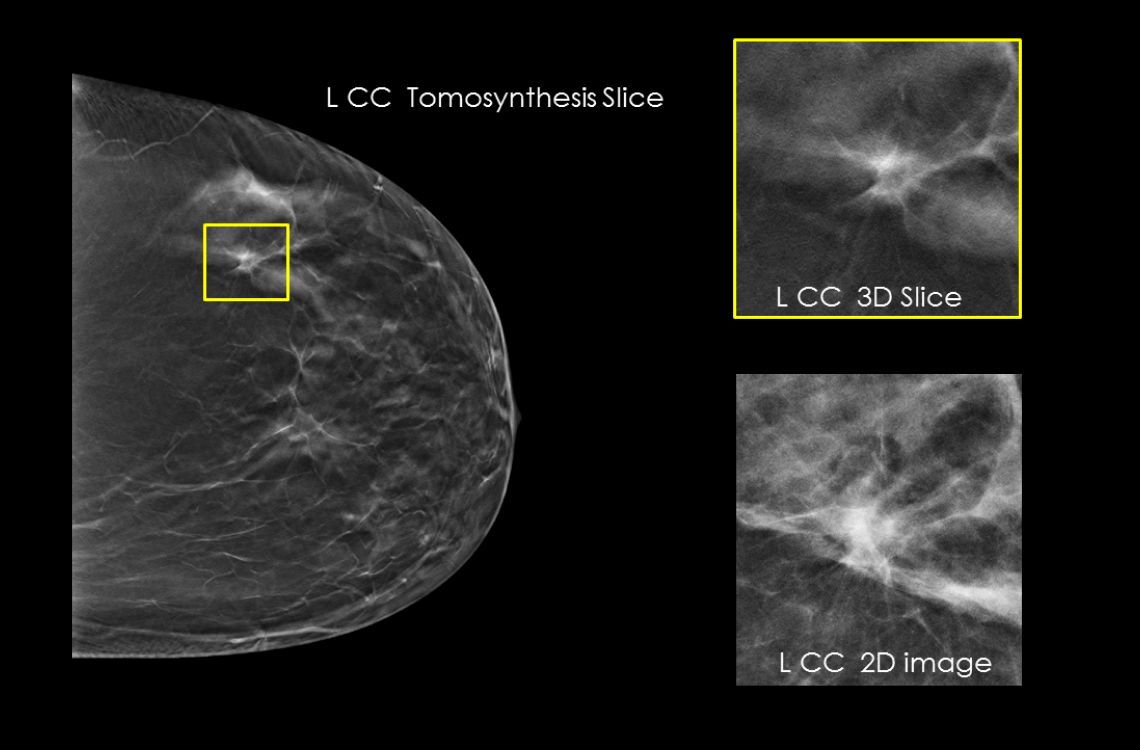

- Proven to detect 20%-65% more invasive breast cancers compared to 2D alone, an average increase of 41%.1

- FDA approved as superior for women with dense breasts compared to 2D alone.2,4

Hologic has further advanced breast cancer screening by producing 2D images from breast tomosynthesis data using C View software, resulting in a Low Dose Genius 3D Mammography exam with superior clinical performance compared with 2D alone.4

This Low Dose Genius 3D Mammography exam is performed in a rapid 3.7 second scan time for greater patient comfort and low patient dose, due to the elimination of 2D X ray exposures. The synthetic 2D images and 3D slices are reviewed together to make clinical decisions or diagnoses part of the Genius 3D Mammography screening exam.